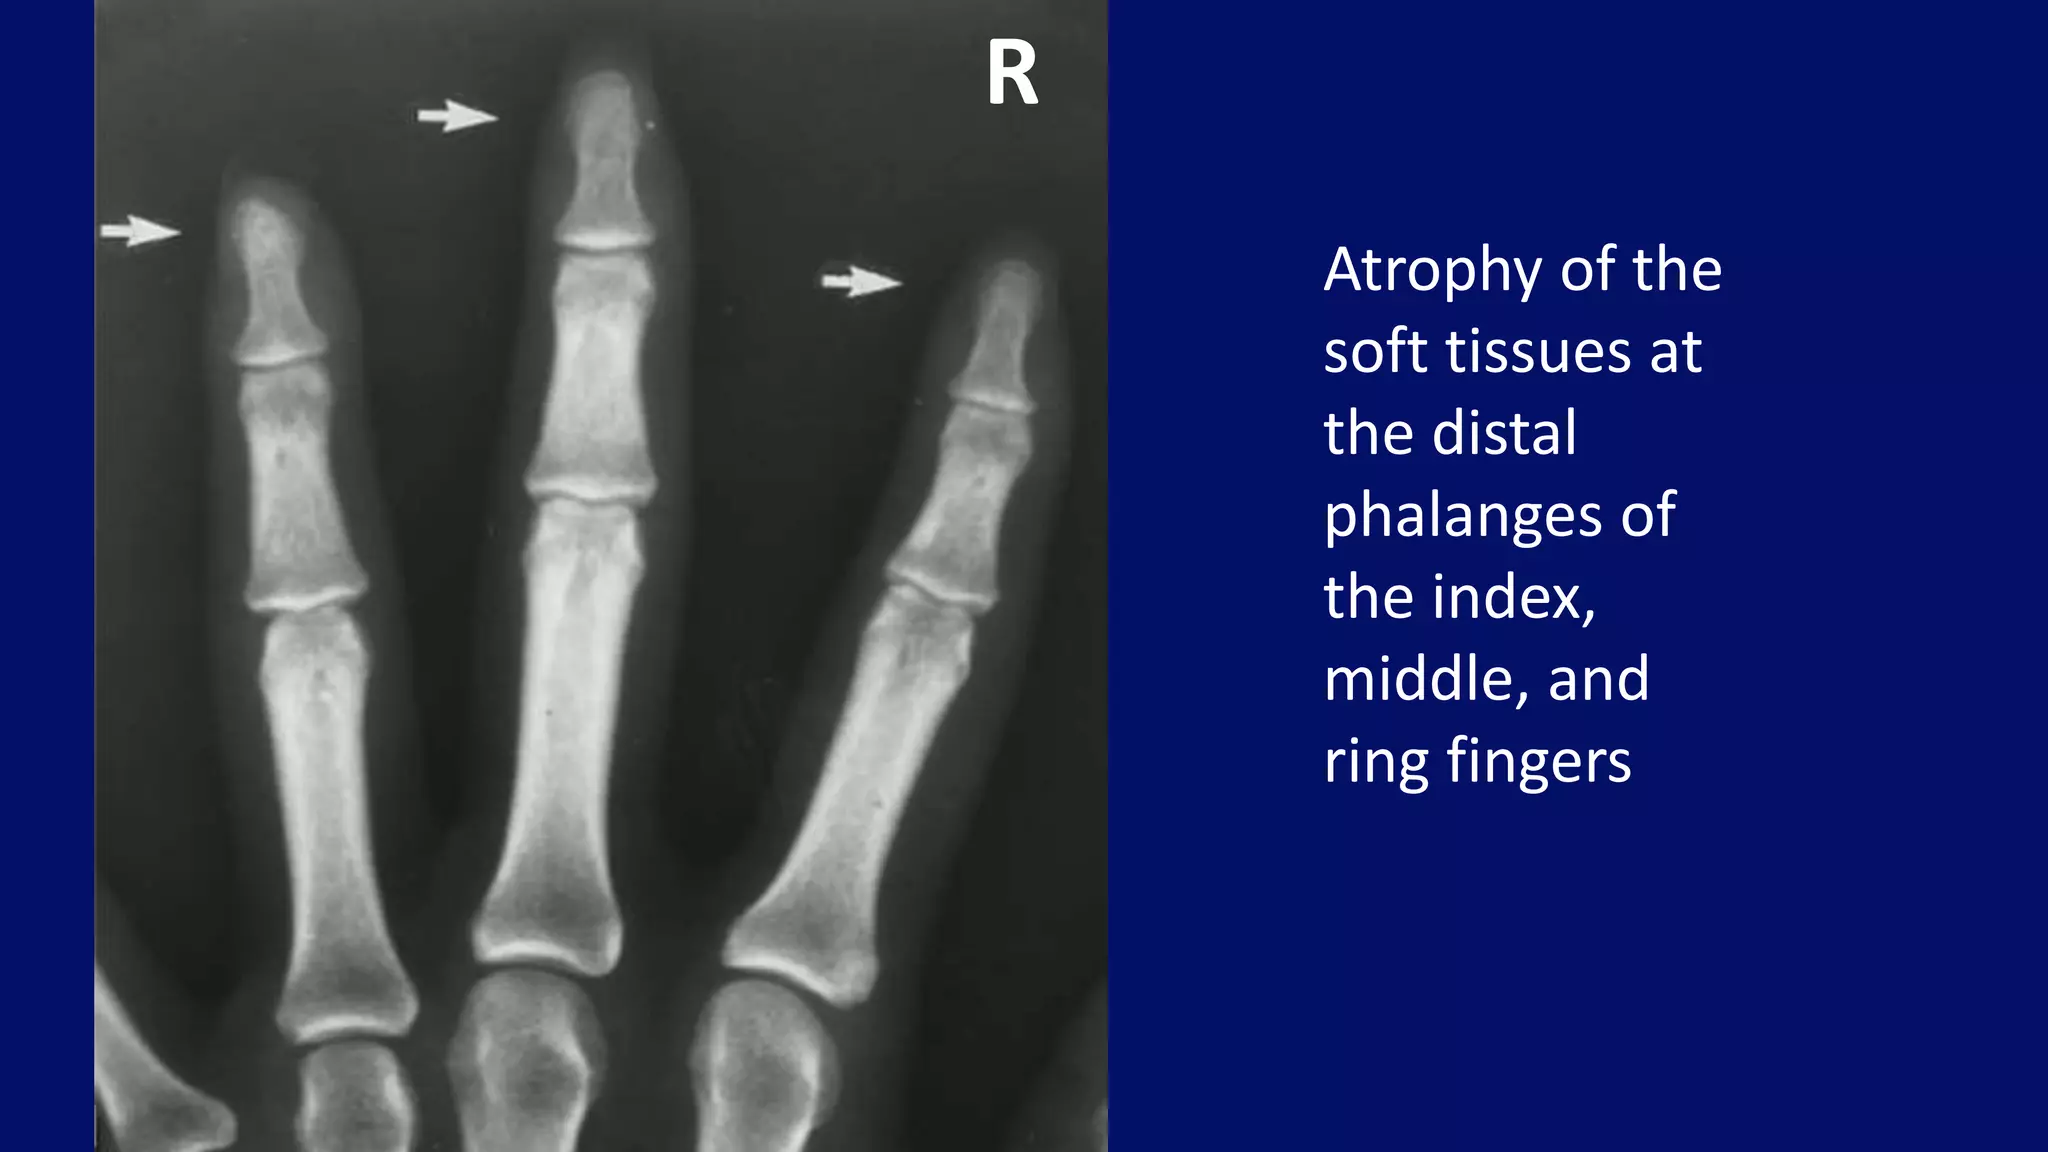

Atrophy of the

soft tissues at

the distal

phalanges of

the index,

middle, and

ring fingers

R

• #78 A 24-year-old woman with scleroderma presented with atrophy of the soft tissues at the distal phalanges of the index, middle, and ring fingers (arrows).